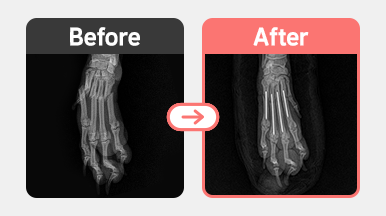

정형센터

치료후기